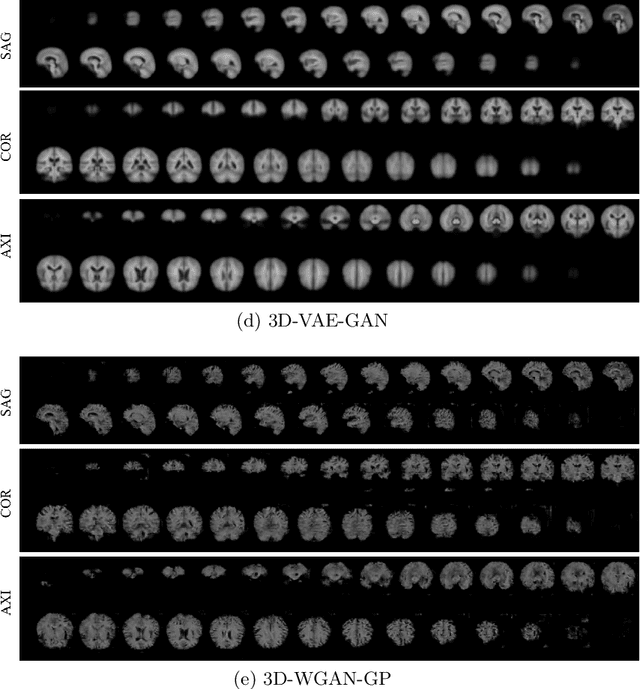

Abstract:As deep learning is showing unprecedented success in medical image analysis tasks, the lack of sufficient medical data is emerging as a critical problem. While recent attempts to solve the limited data problem using Generative Adversarial Networks (GAN) have been successful in generating realistic images with diversity, most of them are based on image-to-image translation and thus require extensive datasets from different domains. Here, we propose a novel model that can successfully generate 3D brain MRI data from random vectors by learning the data distribution. Our 3D GAN model solves both image blurriness and mode collapse problems by leveraging alpha-GAN that combines the advantages of Variational Auto-Encoder (VAE) and GAN with an additional code discriminator network. We also use the Wasserstein GAN with Gradient Penalty (WGAN-GP) loss to lower the training instability. To demonstrate the effectiveness of our model, we generate new images of normal brain MRI and show that our model outperforms baseline models in both quantitative and qualitative measurements. We also train the model to synthesize brain disorder MRI data to demonstrate the wide applicability of our model. Our results suggest that the proposed model can successfully generate various types and modalities of 3D whole brain volumes from a small set of training data.